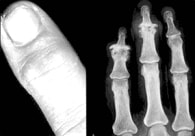

このなかで、とくに変形性関節症はリウマチとよく間違えられやすい病気です。これは中年以降の女性に多く、遺伝的素因が濃厚です。症状としては指の末端の第一関節が硬く腫れるのが特徴で、ときには赤く腫れあがることもあります。このような変化はリウマチでもみられるように、 左右対称性におこります。そして、この指の第一関節の腫れは ヘバーデン結節とよばれます。また、このような変化は指の第二関節におこることもあり、これはブシャール結節とよばれています。X線写真を撮ってみればリウマチとの違いは一目瞭然で、変形関節症では骨のびらん性変化はないかわりに、骨がとげのように出っ張り、しかも骨硬化像がみられます。